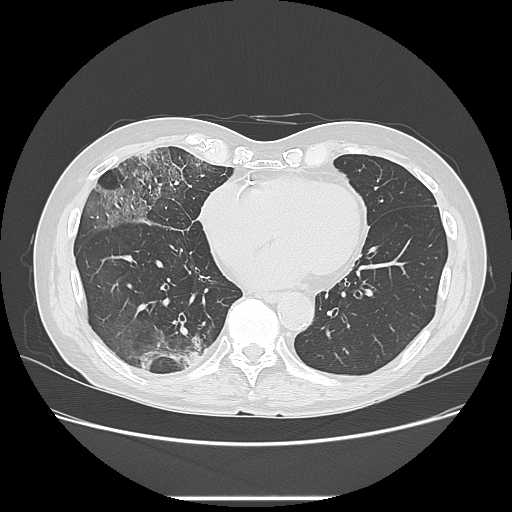

胸部

肺炎